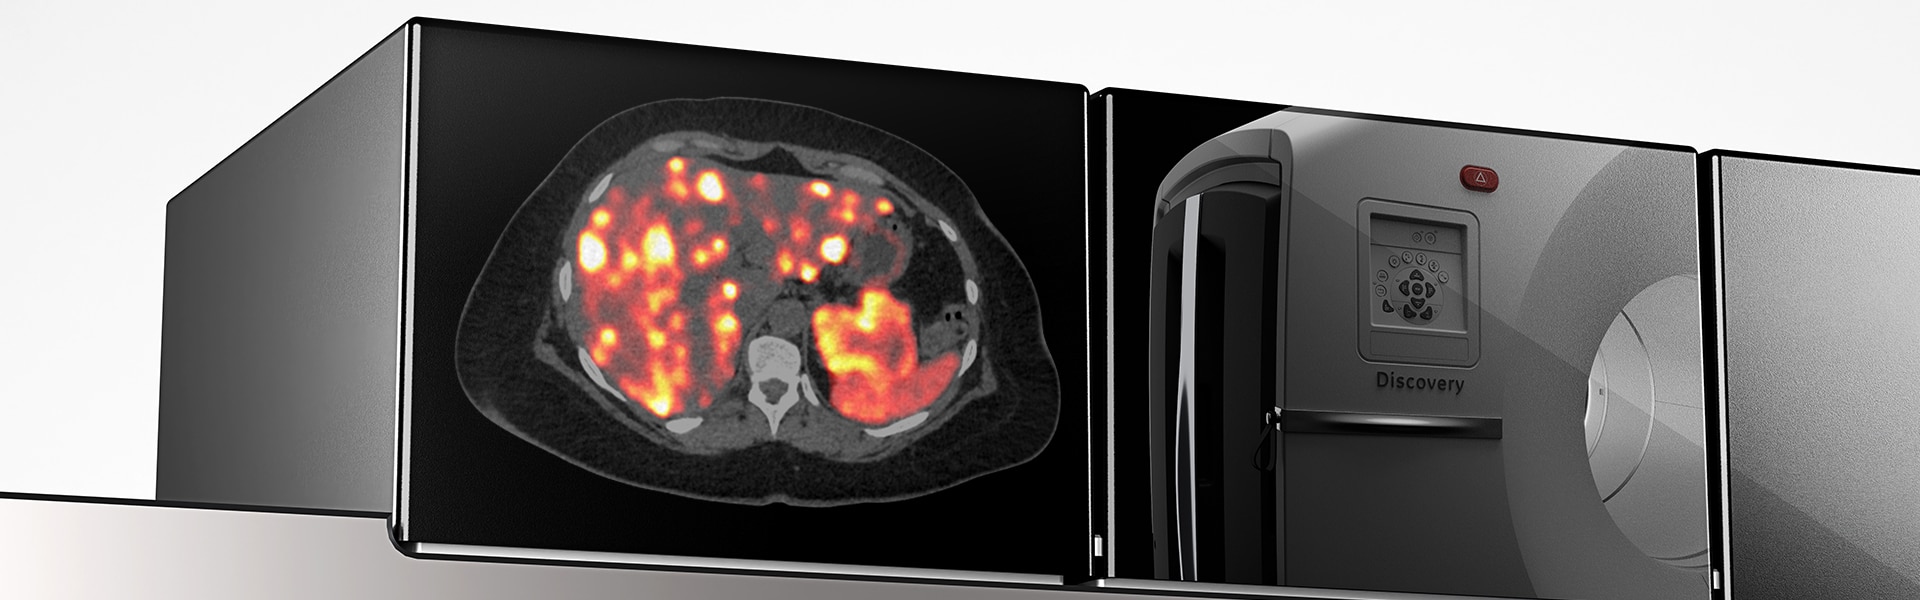

Présentation du système Discovery MI Gen 2

La détection numérique revisitée

Discovery MI Gen 2 a été conçu pour accroître votre productivité

Nouvelle génération de TEP numérique

Nom du produit : Discovery MI Gen2

Utilisation prévue : Le système Discovery MI Gen2 TEP/TDM est destiné à l’imagerie TEP corrigée de l’atténuation par TDM de la distribution des produits radiopharmaceutiques émetteurs de positrons anatomiquement localisée. Il est destiné à l’imagerie du corps entier, de la tête, du cœur, du cerveau, du poumon, du sein, de l’os, des systèmes gastro-intestinal et lymphatique, et d'autres Le système est également destiné à l'imagerie tomodensitométrique diagnostique (CT).